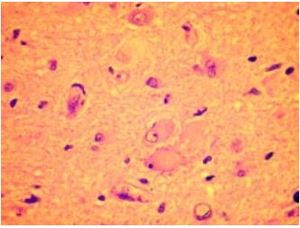

Corteza cerebral. DCF. Células globoides («balonadas») en la sustancia blanca subcortical. Tinción con hematoxilina y eosina.

La DCFT se caracteriza por desorganización laminar de variable intensidad, con la consiguiente pérdida de la organización columnar y, en los casos graves, presencia en el espesor cortical de neuronas gigantes, dismórficas, ectópicas, mal orientadas, con citoesqueleto relevante desorganizado, caóticamente dispersas en todas las capas corticales excepto en la primera capa; asimismo hay proliferación glial astrocitaria, con ausencia (DCF tipo II A) o presencia de bizarras células globoides (balonadas) (DCF tipo II B).

Se caracterizan por excrecencias de tejido glioneuronal en las leptomeninges, persistencia de abundantes neuronas en la capa cortical I (molecular) y en la sustancia blanca subcortical abundantes neuronas ectópicas y células globoides (balonadas) que semejan astrocitos gemistocíticos, ya que tienen citoplasma abundante, ovoide, de contenido semitransparente, eosinófilo. Límites imprecisos entre sustancia gris y sustancia blanca. Hamartomatosis glioneuronal: focos de elementos gliales y neuronales maduros, a veces mezclados con células oligodendroglioides (en 15 % de cerebros con epilepsia).

Recientemente se describe que algunas de las neuronas citomegálicas, comúnmente presentes en la DCF son en realidad interneuronas,[10] lo cual ―además de constituir una reidentificación de esa estructura― tiene significado fisiológico como participante importante en la génesis de las convulsiones, ya que forman parte de circuitos neuronales anormales en la zona afectada.[11][12]

El signo más relevante es el aumento de la frecuencia de descarga en comparación con las interneuronas normales.